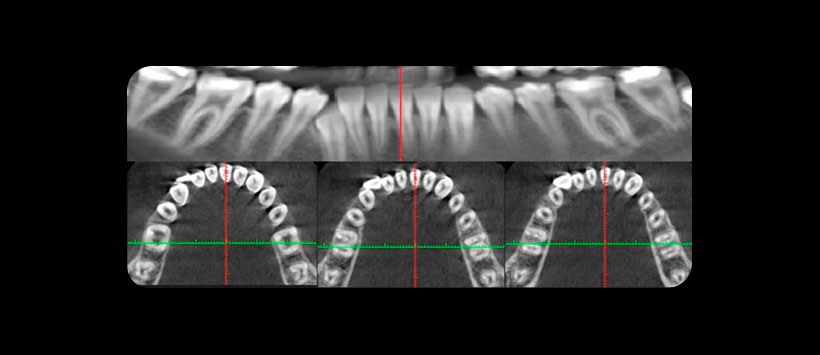

El presente estudio consistió en la evaluación retrospectiva de imágenes CBCT de 231 pacientes adultos (153 con segundos molares mandibulares bilaterales). Dos endodoncistas examinaron 384 segundos molares mandibulares de una población en Tabriz, Irán, para determinar la presencia de canales en forma de C y sus características anatómicas.

Las configuraciones del canal de la raíz se categorizaron en tres niveles diferentes. La aparición bilateral o unilateral de canales en forma de C y su relación con el sexo, la edad y la posición del diente. (Figura 2)

Obteniendo como resultados que, de los 384 segundos molares mandibulares examinados, 82 (21,4%) molares de 58 pacientes tenían una configuración de conducto radicular en forma de C. La prevalencia de canales bilaterales en forma de C fue del 15,6% entre 153 pacientes con segundos molares mandibulares bilaterales. No hubo diferencias significativas en la distribución de los canales en forma de C con respecto al sexo o la edad y solo 4 dientes (4.9%) tenían la misma configuración del conducto radicular desde el orificio hasta el ápice.

En el resto de los dientes, la configuración del conducto radicular transversal cambió a diferentes niveles de la raíz.